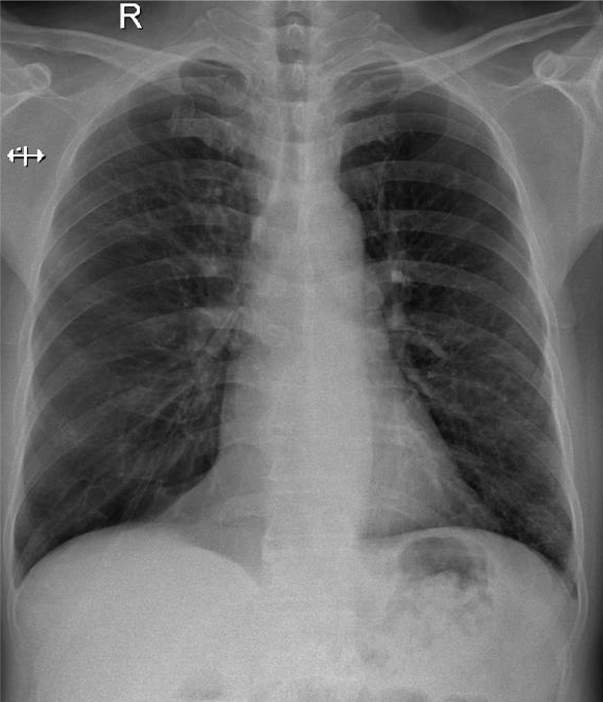

1- Tù góc tâm hoành (P)